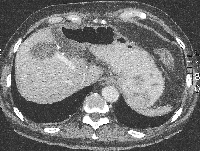

Πρόκειται για άνδρα ασθενή 67 ετών που διαπιστώθηκε ότι έπασχε από αδενοκαρκίνωμα του σιγμοειδούς με 6 συνολικά ηπατικές μεταστάσεις αμφοτερόπλευρα (εικόνες 1, 2). Η διενέργεια PET-CT δεν ανέδειξε εξωηπατική νόσο. Δεδομένου ότι ότι η πρωτοπαθής εστία δεν προκαλούσε αποφρακτικά φαινόμενα και εξαιτίας του εξαιρετικά μεγάλου καρκινικού φορτίου του ήπατος σε σχέση με αυτό το εντέρου, αποφασίστηκε η αντιμετώπιση πρώτα των μεταστάσεων ("liver first" approach). Σύμφωνα με την ανάλυση MeVis (εικόνα 3) η αριστερή ηπατεκτομή οδηγούσε σε 69% ηπατικό υπόλειμμα ενώ η αριστερή εκτεταμένη ηπατεκτομή οδηγούσε σε 28% ηπατικό υπόλειμμα (τριχασμός πυλαίας). Με βάση αυτά τα δεδομένα αποφασίστηκε η κάθαρση του ήπατος από το μεταστατικό φορτίο με ηπατεκτομή και σύγχρονη εστιακή καταστροφή με ραδιοσυχνότητες. Αρχικά, ο ασθενής υποβλήθηκε σε 8 κύκλους χημειοθεραπείας (Avastin, FOLFOX). Ακολούθησε αριστερή ηπατεκτομή, δύο σφηνοειδείς ηπατεκτομές (εικόνα 4) και εστιακή καταστροφή με ραδιοσυχνότητες του παρεγχύματος στο όριο των τμημάτων 5/8 (εικόνα 5), παρεμβάσεις που έφεραν την πλήρη κάθαρση του ηπατικού μεταστατικού φορτίου. Κατόπιν, ο ασθενής υποβλήθηκε σε ακόμα 4 κύκλους χημειοθεραπείας. Η ογκομέτρηση την 4η μετεγχειρητική εβδομάδα ήταν ικανοποιητική (εικόνα 6). Ακολούθως, ο ασθενής υποβλήθηκε σε σιγμοειδεκτομή. Τελικά, η χημειοθεραπεία ολοκληρώθηκε με άλλους 6 κύκλους. Ο ασθενής εξακολουθεί να παραμένει ελεύθερος νόσου στους τακτικούς ελέγχους (δις ετησίως) με κολονοσκοπήσεις και CT.